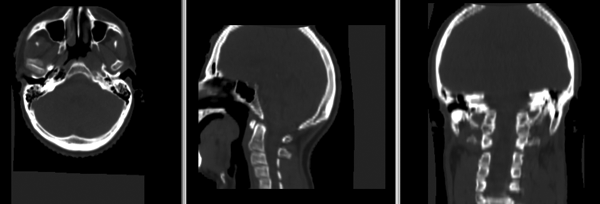

| − | [[Image:Head&Neck_reg_Anim. | + | [[Image:Head&Neck_reg_Anim.gif]] |

- initial discussion with Marta: issues with stopping criterion, FOV and DOF constraints, both inter- and intra-subject registration; collecting dataset for trials. PM: Precision ***, Speed *, Robustness **